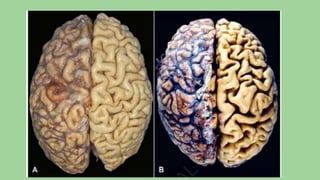

The document summarizes various mechanisms of cell injury and adaptation. It discusses how cells respond to physiological stresses through reversible changes like hypertrophy, hyperplasia, atrophy, and metaplasia to maintain homeostasis. Irreversible injury can result from oxidative stress, calcium influx, ATP depletion, and mitochondrial or membrane damage, leading to necrosis or apoptosis. Reversible injury involves structural and functional changes while irreversible injury culminates in cell death.